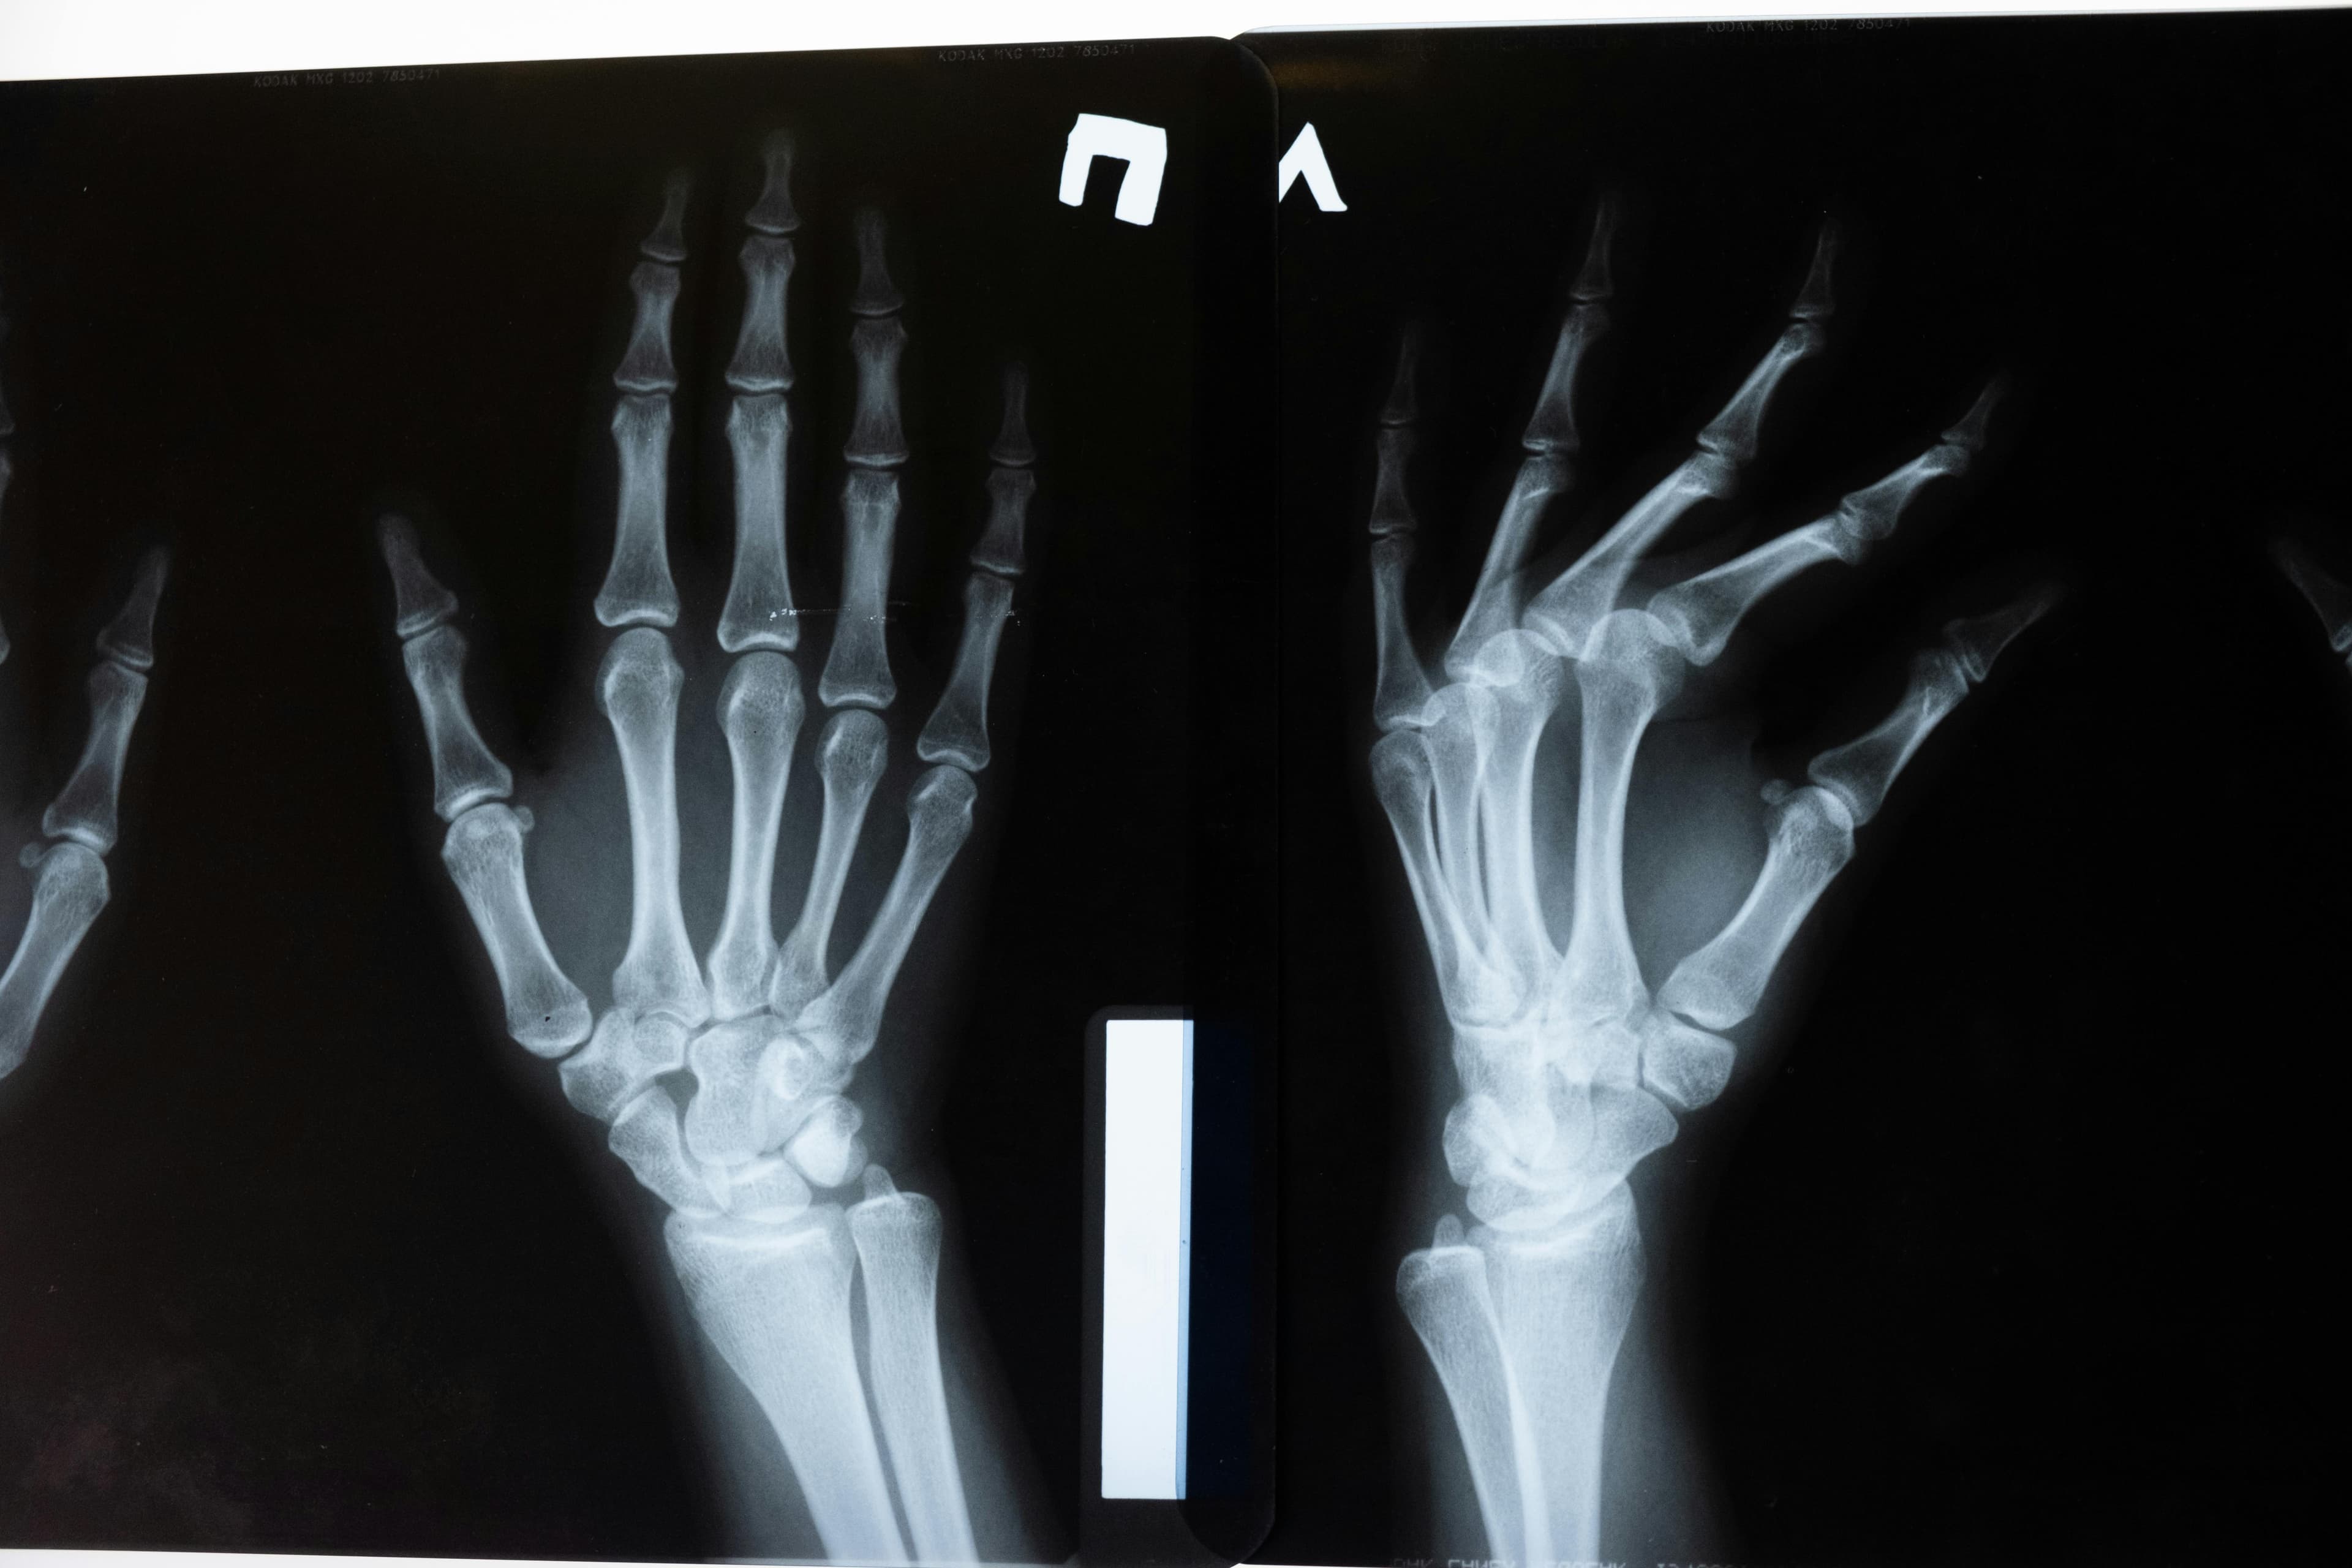

Radiographic Absorptiometry (RA)

RA uses standard X-ray equipment with a reference wedge to estimate bone density.

- Advantages: Widely available, relatively inexpensive

- Limitations: Less precise than DEXA, limited to peripheral sites

A study found that RA could be cost-effective as a pre-screening tool, potentially reducing the need for DEXA scans by up to 19% in certain populations.